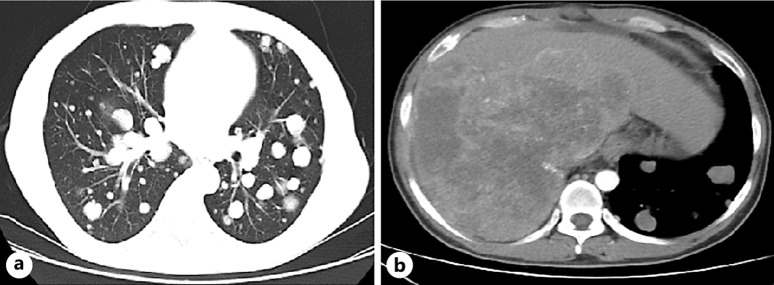

Case presentation: A 41-year-old male with stage IVC sigmoid colon adenocarcinoma presented with recurrent high-grade fever (up to 40.4°C), chills, and markedly elevated inflammatory markers (C-reactive protein [CRP]: 202.0 mg/L; procalcitonin: 3.44 ng/mL) over a 2-week period. Comprehensive infectious evaluations, including cultures, antigen testing, and imaging, were all negative. Empirical antibiotics and conventional nonsteroidal anti-inflammatory drugs (NSAIDs) (ibuprofen, diclofenac) failed to achieve sustained defervescence. After ruling out infectious and autoimmune causes and considering chemotherapy-induced tumor lysis, NF was suspected. Administration of 500 mg of naproxen (suppository) led to rapid normalization of temperature (36.4°C) and sustained defervescence. A corresponding decrease in inflammatory markers (CRP: 51.6 mg/L; procalcitonin: 1.70 ng/mL) further confirmed the diagnosis.